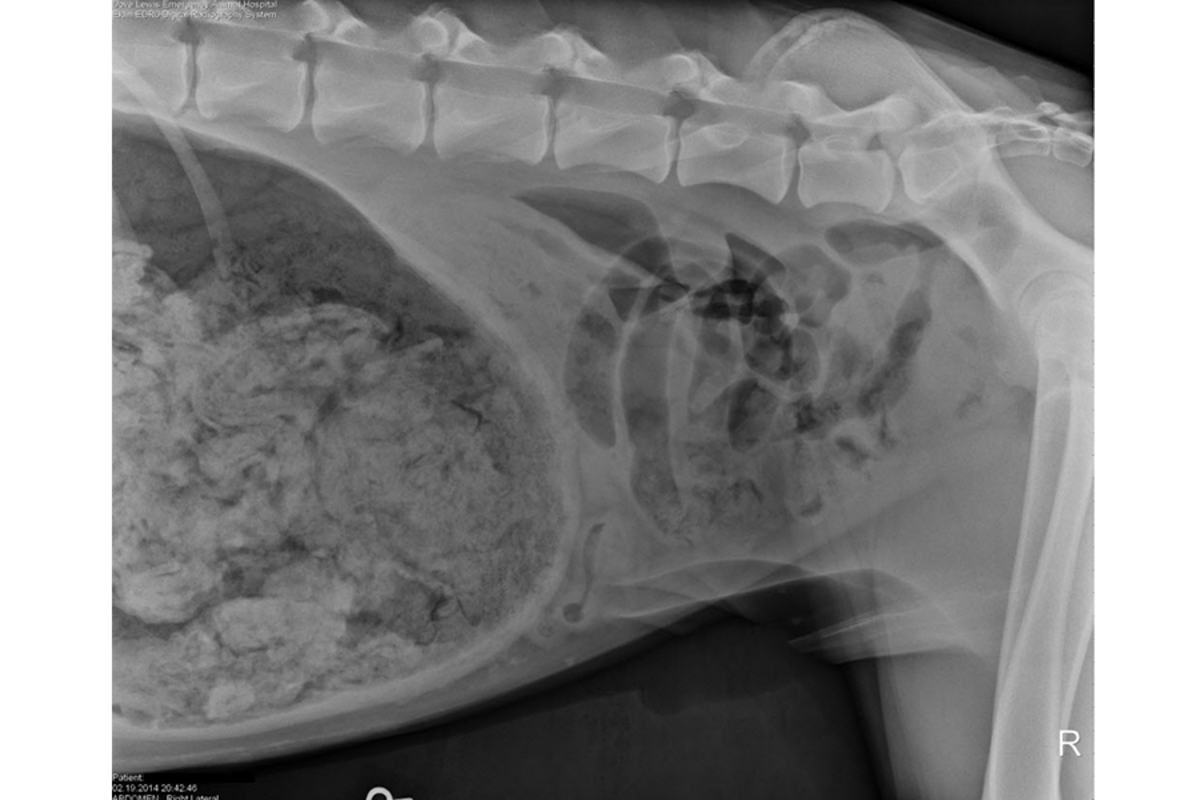

A 3-year-old Great Dane was miserable, retching and vomiting, when his owners rushed him to DoveLewis Emergency Animal Hospital, in Feb. X-rays showed a stomach full of what was described as 'a large quantity of foreign material.' Nearly two hours of surgery later, Dr. Ashley Magee said the dog had consumed 43 陆 socks.

X-rays showed a stomach full of "a large quantity of foreign material." Nearly two hours of surgery later, Dr. Ashley Magee had the answer 鈥 the dog had consumed 43 陆 socks.